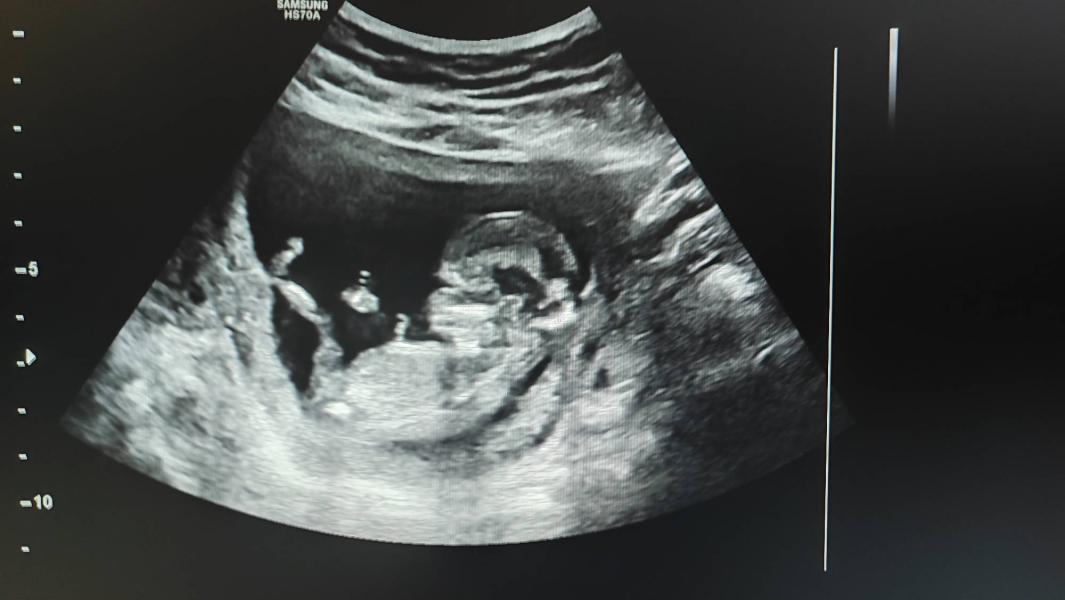

Девочки оставлю на память❤️ на узи и акушерскому 13 нед. и 1 день.

Сегодня 21 марта 24 год была на первом скрининге в 3ем роддоме. Сразу скажу фото не дают, мужа не пускают, но делают стоп кадр и разрешают фотографировать ( это все только 1ый скрининг) . Посмотрели очень внимательно, после осмотра рассказала все и повернула экран и по-всякому показала лялюшу)) и как так крутиться, как ручками машет и как ножки вытягивает😊🥰 конечно я не смогла сдержать слез, реакция врача хорошая, но попросила не ...